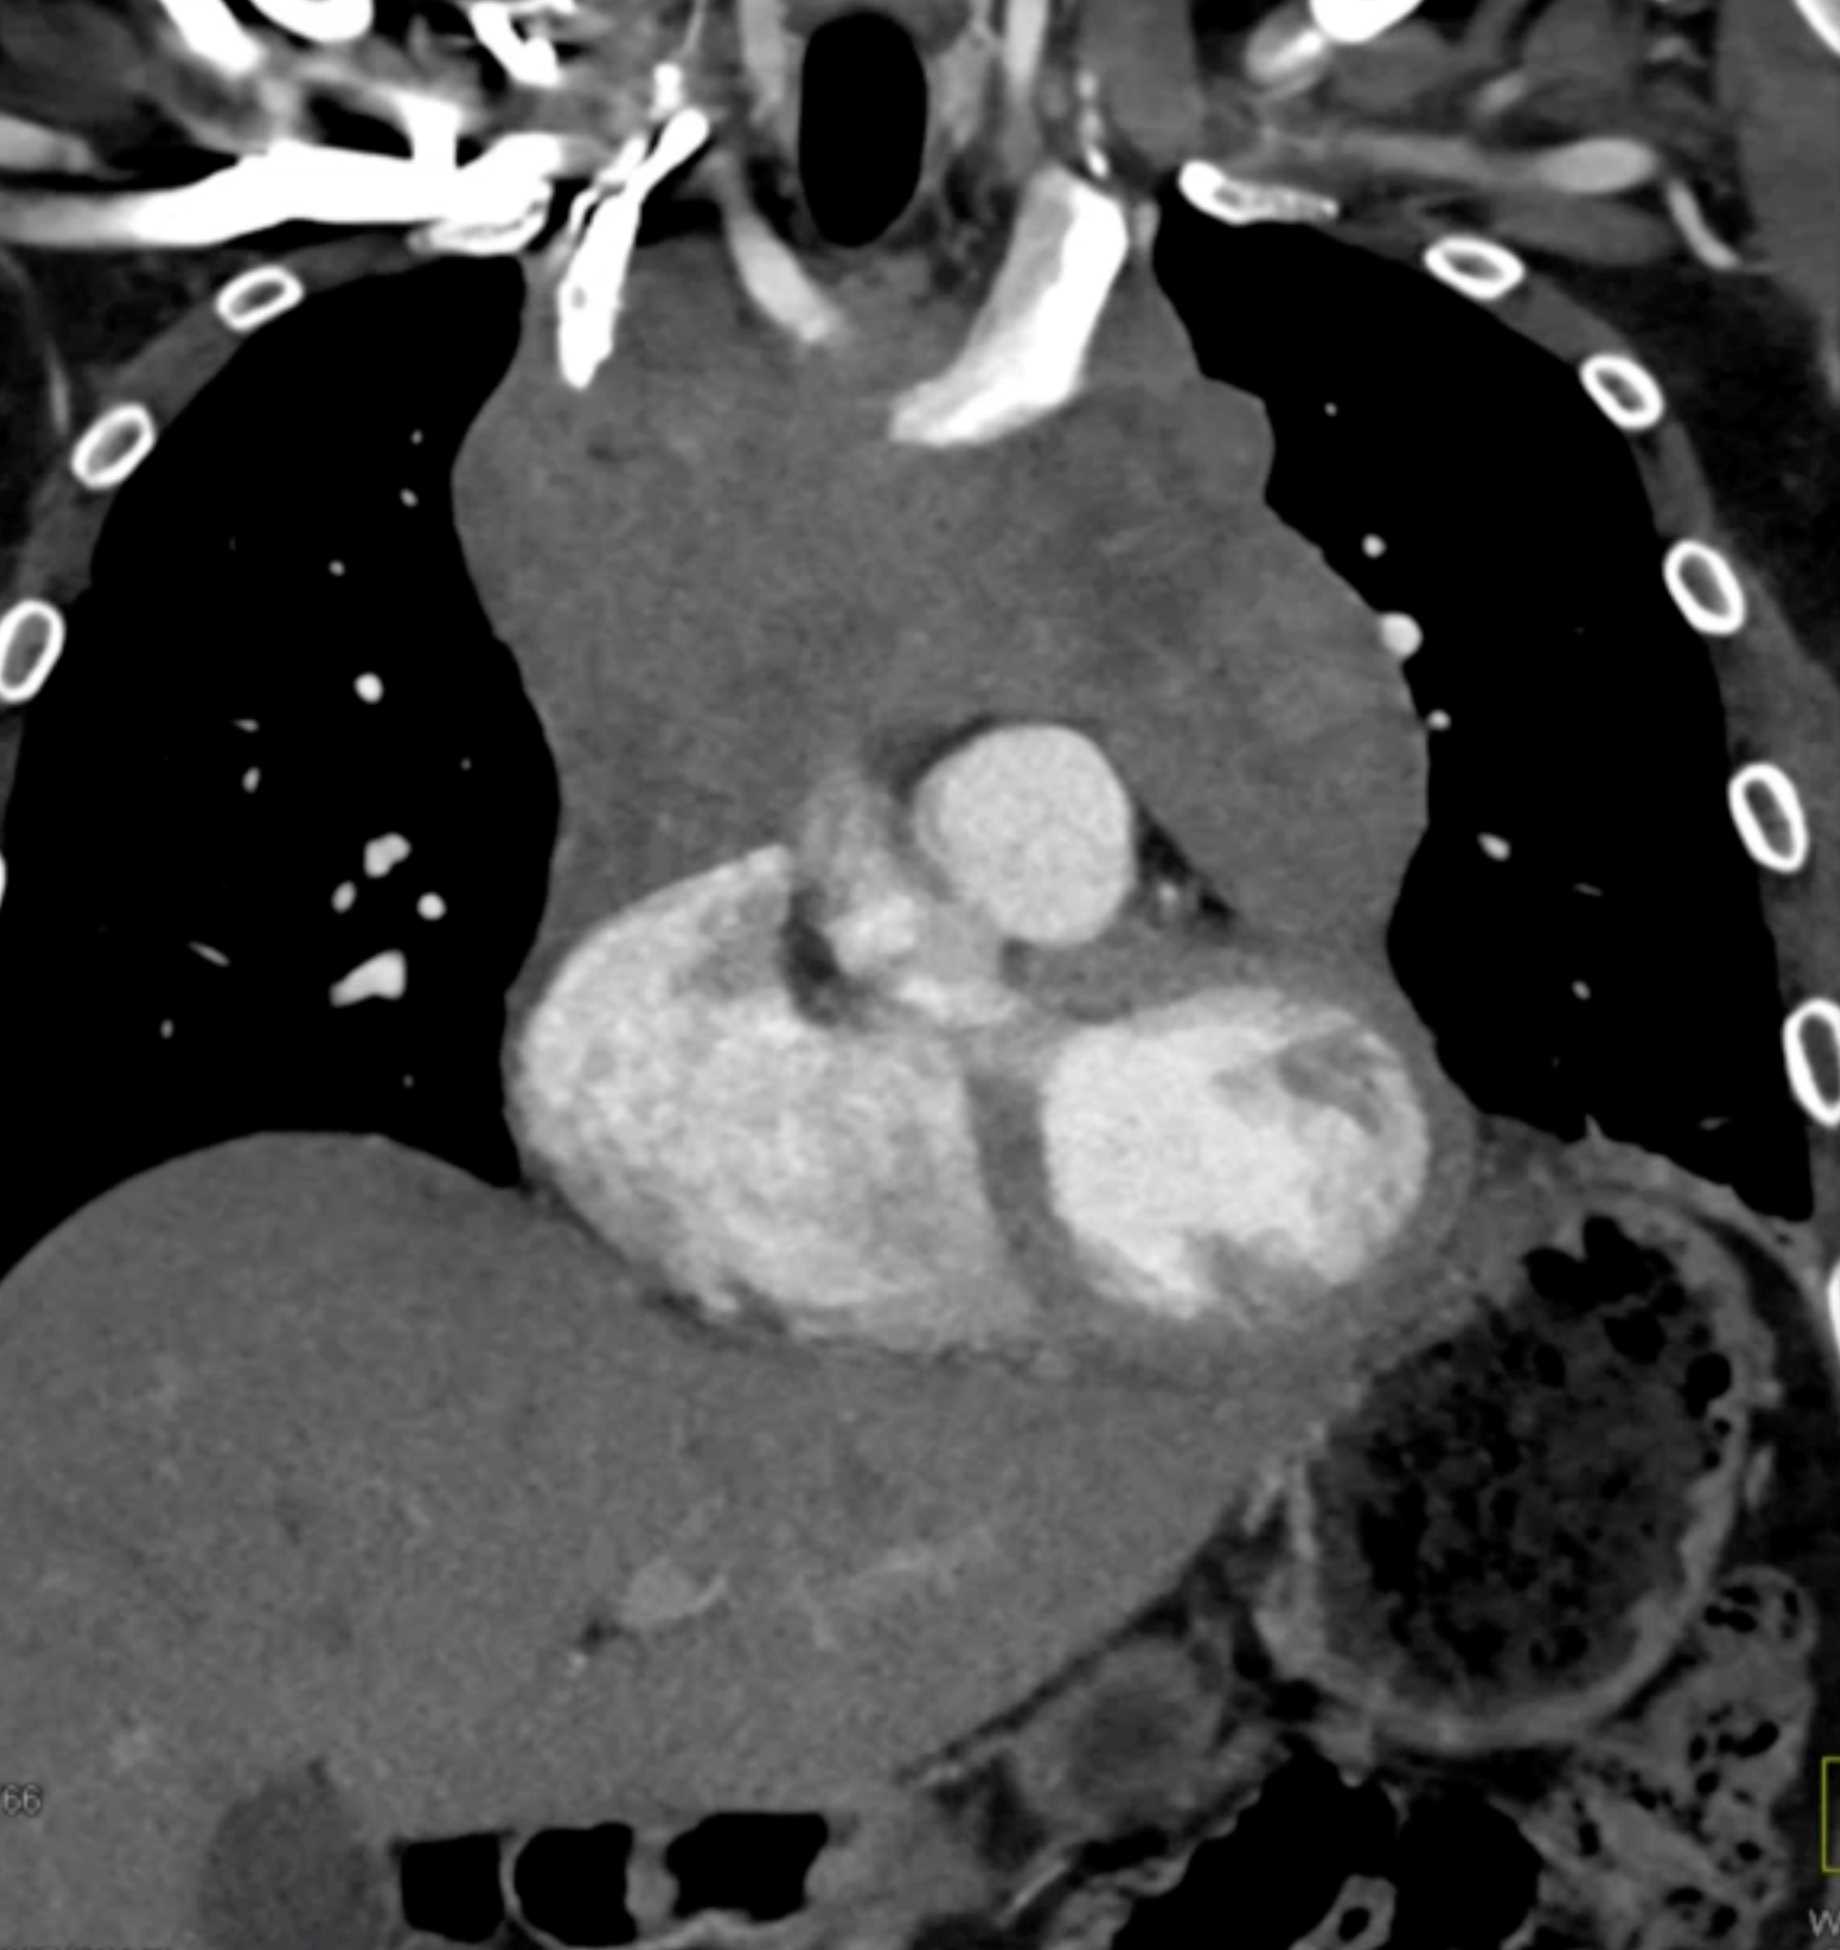

Thymic Carcinoma